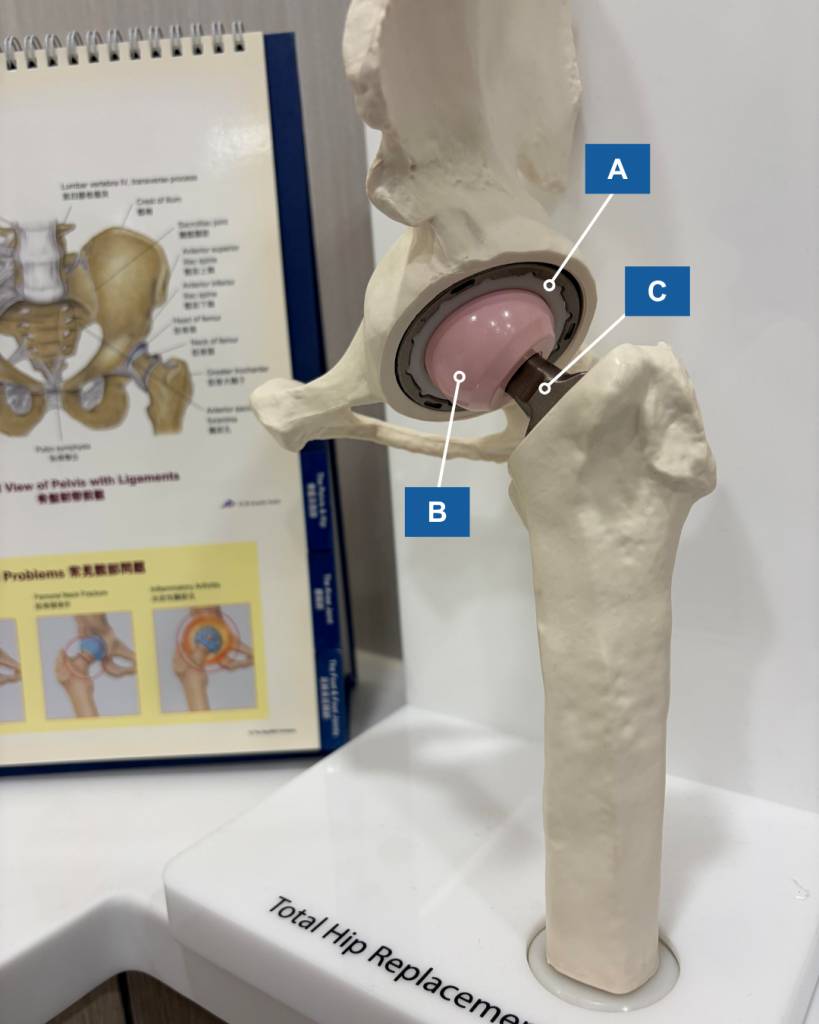

髖關節置換手術,顧名思義就是把磨損退化的髖關節完全更換為人工關節假體(見圖二)。

手術過程中,骨科醫生會於患者的臀部側面打開一個約10至15厘米的傷口,然後使用手術儀器,把磨損的髖臼打磨成為碗狀,先放入髖臼假體及襯墊,然後把變形的股骨頭移除,再把股骨假體植入股骨上端內。完成整個人工關節組裝後,醫生會把人工關節復位,將髖臼和股骨假體結合。